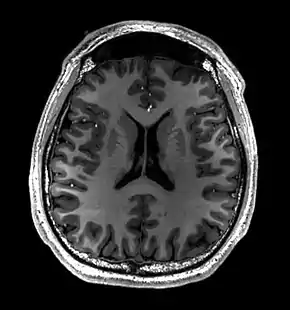

- Normal axial T2-weighted MR image of the brain